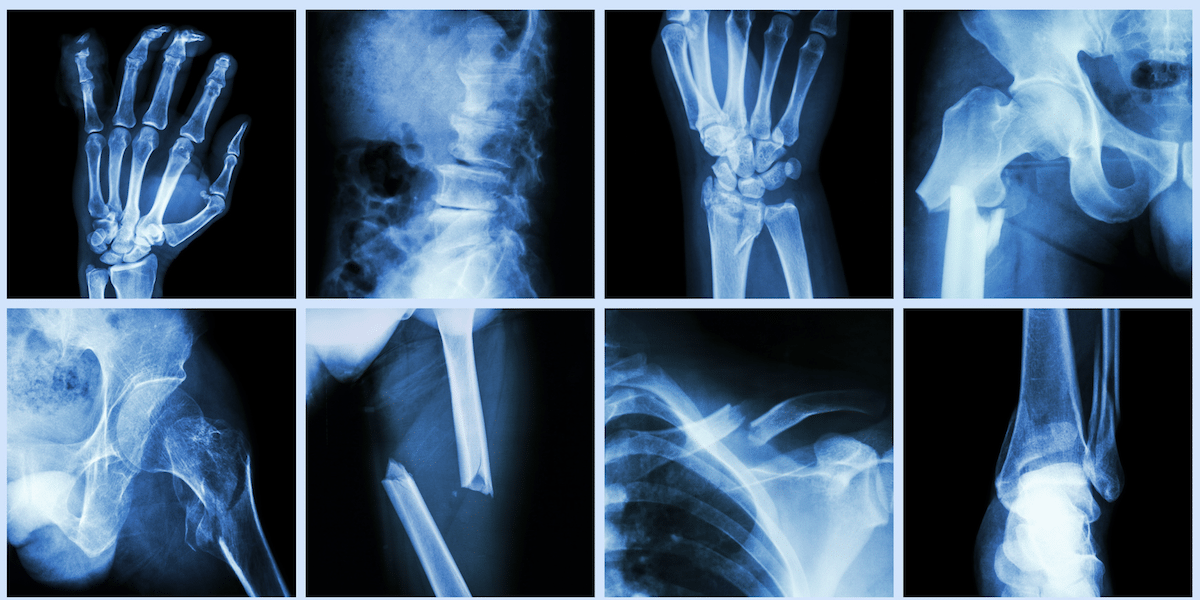

Vitamin D And Calcium For Fracture Healing . Combined supplementation with 800 iu of vitamin d per day and 1200 mg of calcium per day has been recommended for prevention of fractures in older adults living. To evaluate whether the association between calcium, vitamin d, or combined calcium and vitamin d supplements and fractures was modified by clinical characteristics, we specified. Vitamin d supplementation represents a potential strategy for treating compromised fracture healing in osteoporotic patients. Vitamin d and calcium supplementation, in addition to antiosteoporosis treatment after surgery or conservative treatment, can ensure. Two clinical studies found a positive effect of vitamin d supplementation and calcium, of increased bone mineral density or respectively. The current review summarises the state of the literature, focusing on the role of calcium and vitamin d in fracture healing and. However, the effect of vitamin d on bone healing following a fracture is a much less studied concept. Find out the optimal vitamin d dose, the causes and signs of vitamin d deficiency,. Learn how vitamin d and vitamin k2 work together to support bone health and fracture repair.